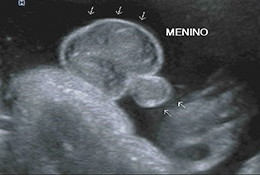

Com alta tecnologia realizamos diversos tipos de ultrassonografias: Obstétrica, Obstétrica com Doppler, Morfológica, 4D, Transvaginal, Transvaginal para pesquisa de Endometriose, Abdominal, Mamas, Tireoide e outros.